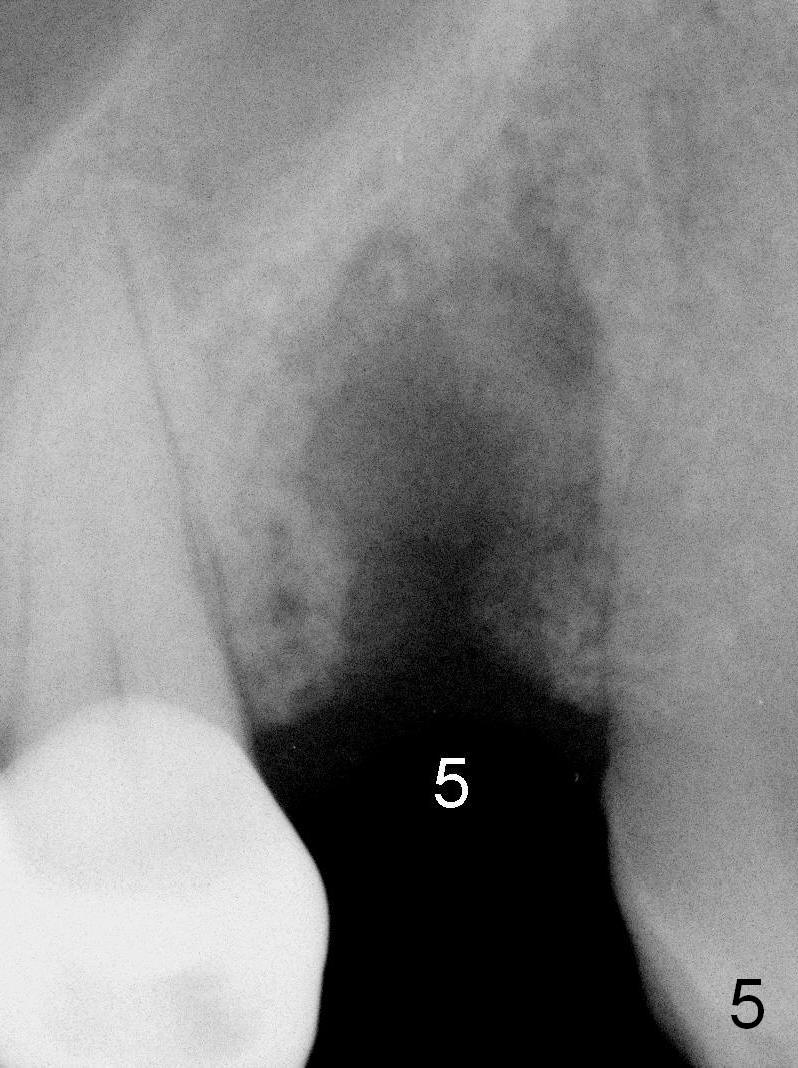

A 68-year-old man has pain and swelling associated with the tooth #5 (Fig.1). The fistula (*) is connected to the periapical radiolucency using a gutta percha (Fig.2 <). There are deep pockets distobuccal and lingual. The lingual root is found to have oblique fracture upon extraction. The distobuccal plate perforates (Fig.3). Collagen plug is placed. The buccal plate is concave (Fig.4) and socket density is low 2.5 months post extraction. Three months post extraction a 4.5x8 mm Bicon implant is placed after reamer and osteotome osteotomy (Fig.6). Bone density around the implant appears to increase 5 months post placement (Fig.7). Porcelain-fused-to-metal crown is cemented 2 weeks later. Bucco-occlusal porcelain chips 2 months post cementation. The patient decides to redo the crown. PA is taken before crown removal (Fig.8: 3 year 10 months post cementation). When a straight abutment is removed (Fig.9 A), a 15° angled abutment has to be used (Fig.10 red) for restoration.